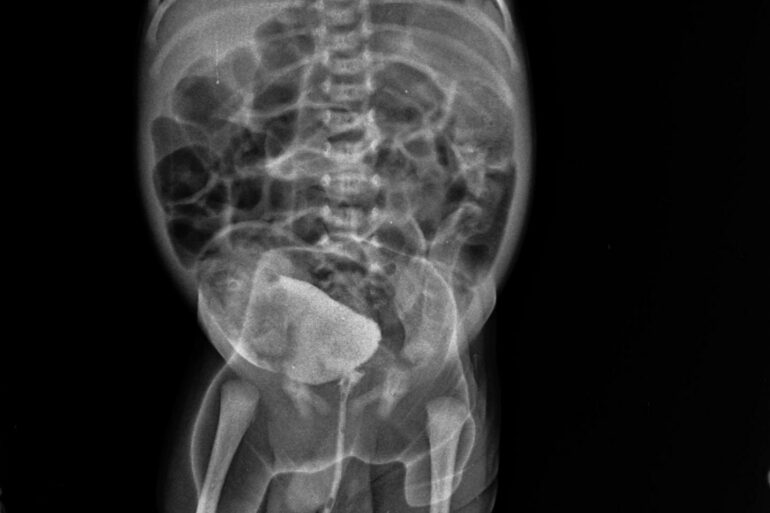

Let us share another paediatric case. Hirschsprung’s Disease is the most common cause of lower intestinal obstruction in neonates. Hirschsprung’s Disease, also known as aganglionic megacolon, ... read more

Let me share another case of congenital/Developmental anomaly, Hirschsprung’s Disease The patient is from the Unnao district. The patient was facing trouble with constipation, which was very painful. ... read more